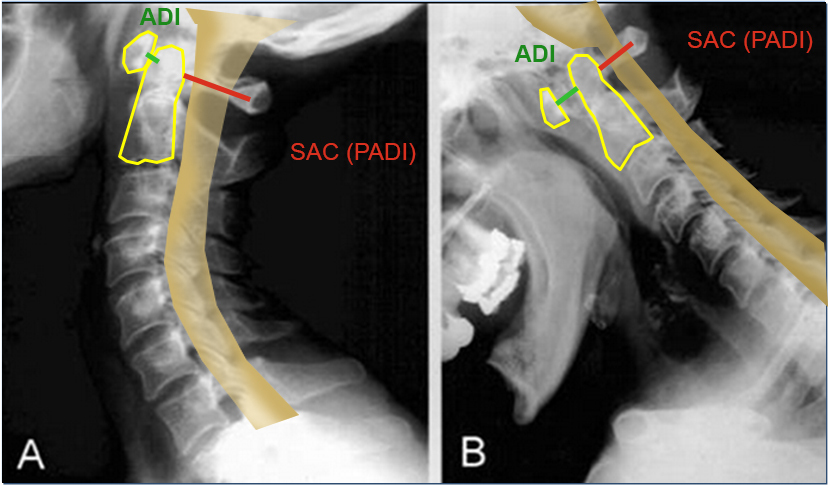

PADI>14mm

Boden and associates’ article presents compelling evidence that patients with rheumatoid arthritis and neurologic deterioration in C1-2 instability are more likely to achieve some improvement if the posterior atlanto-dens interval is greater than 10 mm on preoperative studies. All the patients in their series who had neurologic deterioration and a preoperative posterior atlanto-dens interval of greater than 14 mm achieved complete motor recovery.

Boden et al. “The most important predictor of the potential for neurological recovery after the operation was the preoperative posterior atlanto-odontoid interval (PADI). In patients who had paralysis due to atlanto-axial subluxation, no recovery occurred if the PADI was less than 10mm, whereas recovery of at least one neurological class always occurred when the PADI was at least 10mm. All patients who had paralysis and a PADI or diameter of the subaxial canal of 14mm had complete motor recovery after the operation.” They found no correlation with the anterior atlanto-odontoid interval (ADI) with the severity of paralysis or the potential for recovery.

Xrays to determine AADI and PADI:

- 3.5 mm on flex/ex

- PADI <14 mm more sensitive than AADI measurement for spinal cord compression in patients w/ RA. More sensitive for identifying patients at risk of neuro injury.

Surgery:

- - C1 lateral mass-C2 pedicle/pars fixation (Harms construct) using polyaxial screws

□ Lower rates of vert and C2 n. injury

□ Strongest biomechanical construct

Does not require C1-2 reduction

How well did you know this?

Xrays determine mechanical instability: c1-c2 relationship.

* AADI >9-10 mm= surgery due to risk of neurologic injury

* PADI <14 mm= surgery due to risk of neurologic injury

* 3.5 mm on flexion/ext views, though radiographic instability is common in RA and not necessarily indication for surgery.

PADI <14 mm more sensitive than AADI measurement for spinal cord compression in patients w/ RA. More sensitive for identifying patients at risk of neuro injury.

AAOS: patients with rheumatoid arthritis and neurologic deterioration in C1-2 instability are more likely to achieve some improvement if the posterior atlanto-dens interval is greater than 10 mm on preoperative studies. All the patients in their series who had neurologic deterioration and a preoperative posterior atlanto-dens interval of greater than 14 mm achieved complete motor recovery.